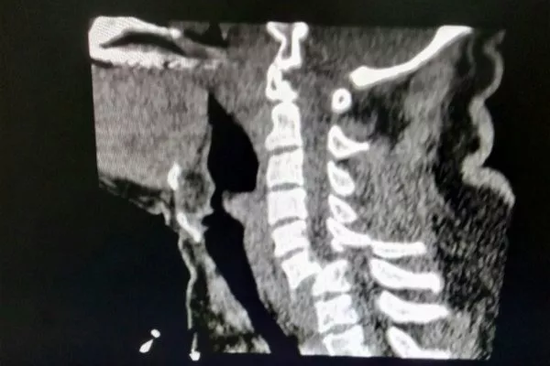

脊柱外科医生马凯教授告诉记者,经急诊诊断,刘先生颈部6、7椎体脱位,颈髓损伤,四肢完全瘫痪。后经过脊柱外科会诊,为刘先生做了颈椎减压复位固定椎间植骨融合内固定术。目前刘先生的双臂力量较术前有所好转,能够动。

马凯教授介绍,这是一种比较严重的颈椎骨折错位,好在位置比较靠下,假如骨折的部位再升高一到两个截断的话,患者可能在现场就会失去生命体征。